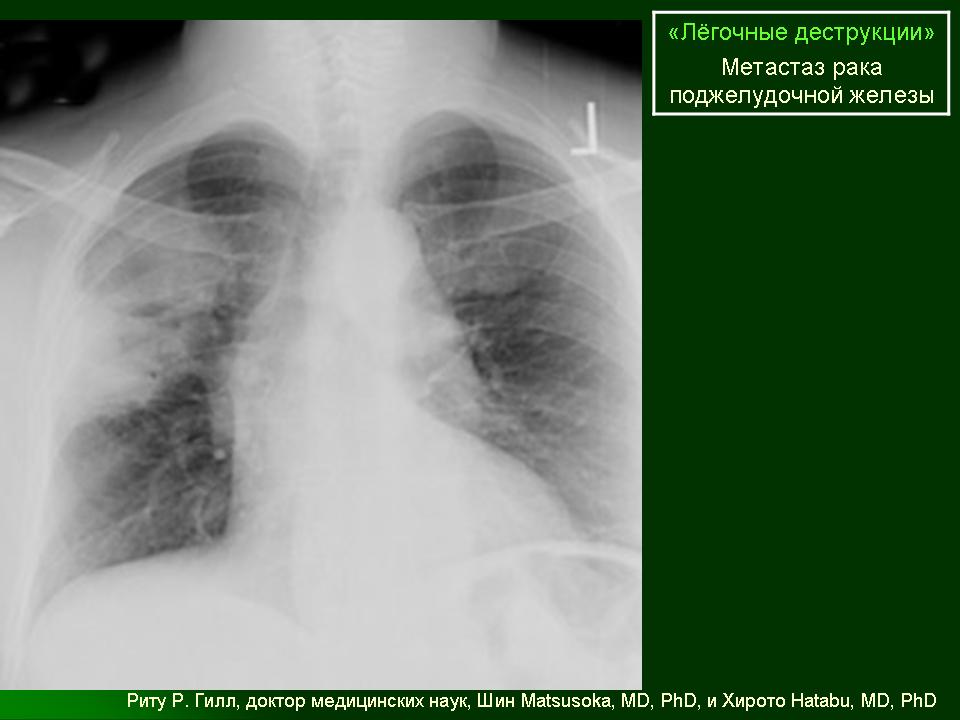

Онкология. ОГК. Полостные (кавитирующие) метастазы. "Атипичные" метастазы. +

Множественные метастазы.